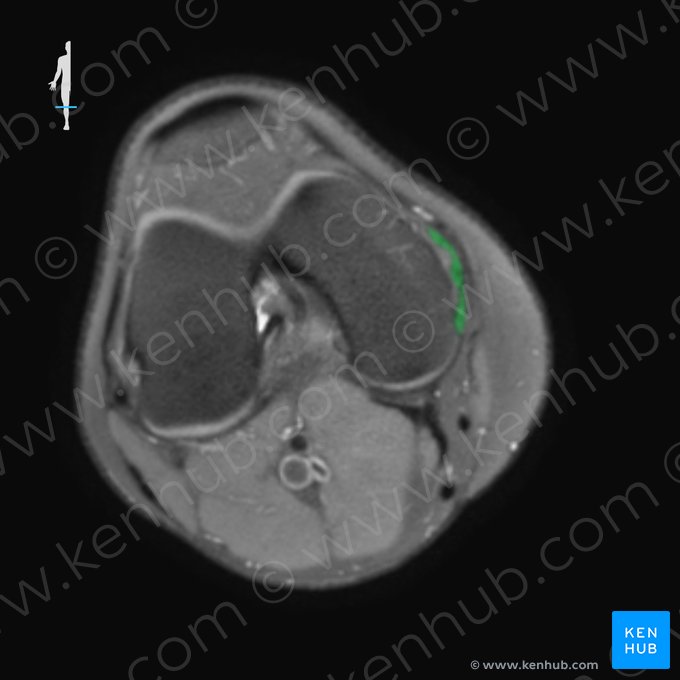

Rodilla (RM)

Una secuencia muy útil para evaluar la articulación de la rodilla (y la mayoría de las estructuras musculoesqueléticas) es la secuencia potenciada en densidad de protones, también conocida simplemente como DP. Las imágenes en DP generalmente muestran una intensidad de señal similar entre los líquidos y las grasas, los cuales aparecen de color gris claro. Esto ayuda a identificar esta secuencia.

Las imágenes a continuación muestran las principales estructuras que pueden ser identificadas en la RM de rodilla usando secuencias DP: